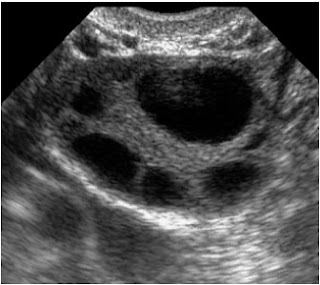

On Tuesday morning I had the Ultra sound back at the IVF

clinic and it showed no signs of OHSS! So they sent me home... where I have been ever since.